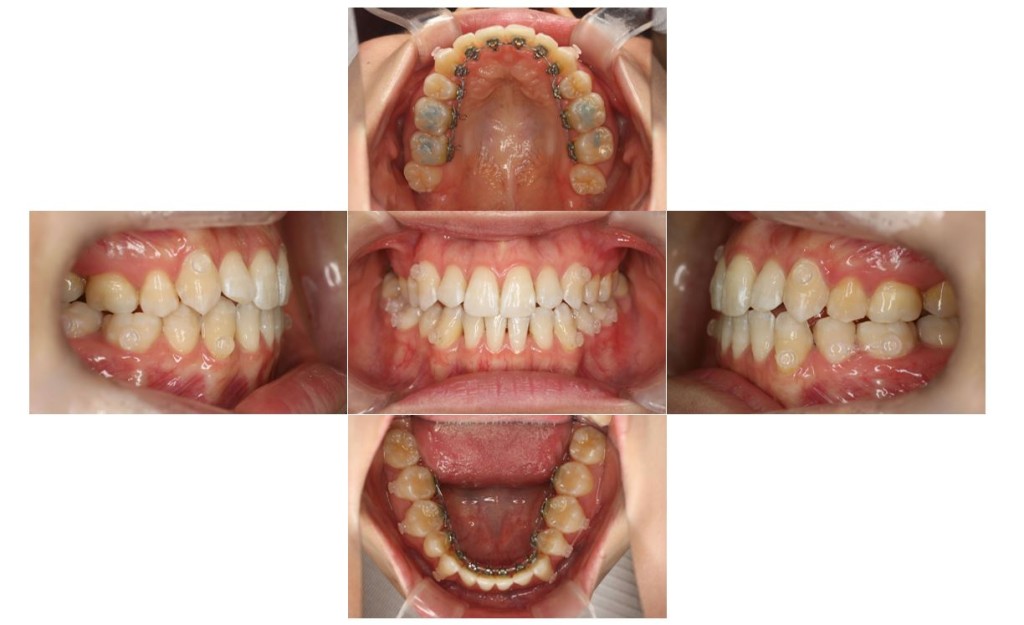

| 主訴 | 下の歯が、上の歯より前に出ていて顎が出ているのが気になる。受け口を治したい。でこぼこもあり歯磨きにしくいので、虫歯予防のためにも綺麗に並べたい。 |

| 治療費用 | 検査・診断:38,500-/裏側矯正治療:1,397,000-(※全て税込) |

| 治療期間 | 2年2ヶ月(29回) |

| 抜歯 | 有(左上4、左下5、上下親知らず4本) |

| 矯正の装置 | 裏側矯正(舌側矯正) |

| 副作用、リスク | 歯肉退縮,歯根吸収,疼痛,咬合の違和感,装置の違和感,虫歯,歯肉炎 |